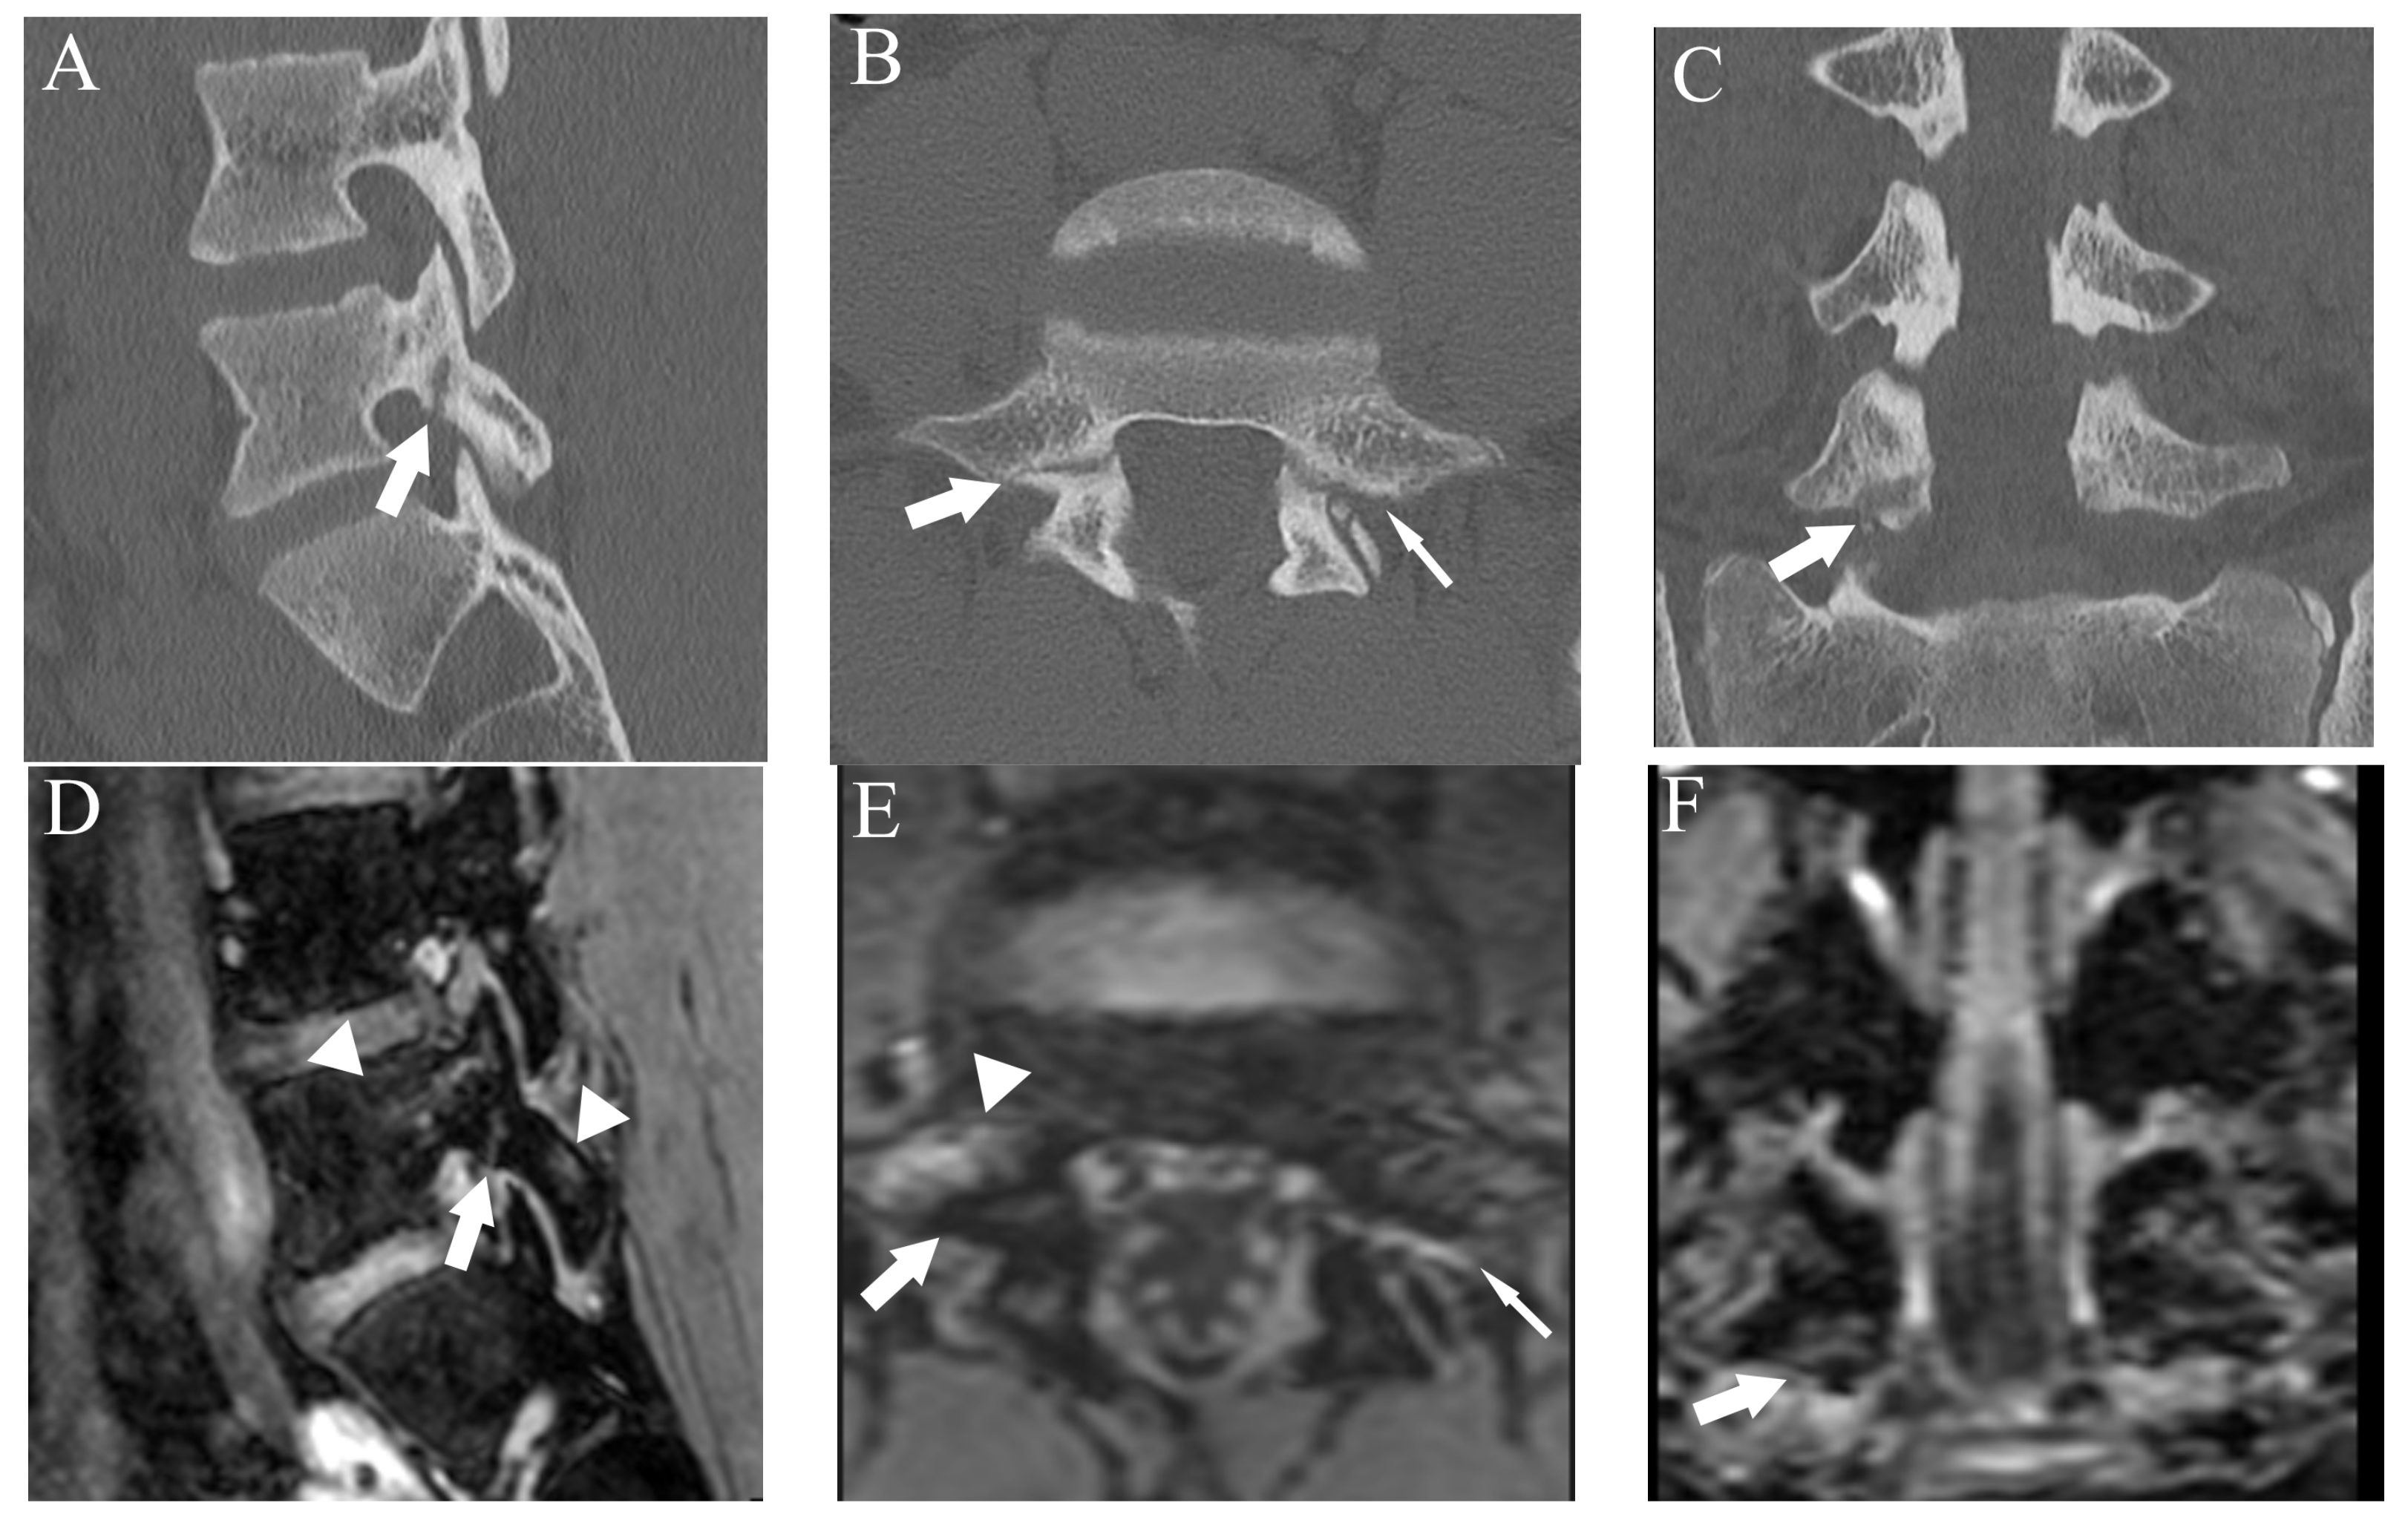

Figure 6.

Comparison of grade 2 fracture at the right pars interarticularis at L5 from a 14-year-old male in multiple planes between CT and DESS. (A–C) CT shows grade 2 fracture on the right pars interarticularis on the right-sided sagittal, axial, and coronal plane, respectively (arrows). On the axial plane, fracture of the left side is also delineated (thin arrow). (D–F) DESS shows grade 2 fractures comparable to CT on the right-sided sagittal, axial, and coronal plane, respectively (arrows). The sagittal and axial images delineate BME around the fracture (arrowhead), and the left pars interarticularis fracture is also delineated on the axial image (thin arrow).

Agreement of fracture grading with CT showed excellent (Kappa = 0.90 (95% confidence interval (CI): 0.84, 0.96)) on DESS but T1WI showed substantial (Kappa = 0.67 (95% CI: 0.61, 0.73)) agreement. Compared to reference fracture grade created by CT, nine cases were assigned a lower grade by DESS, whereas three were assigned a higher grade (Figure 7).